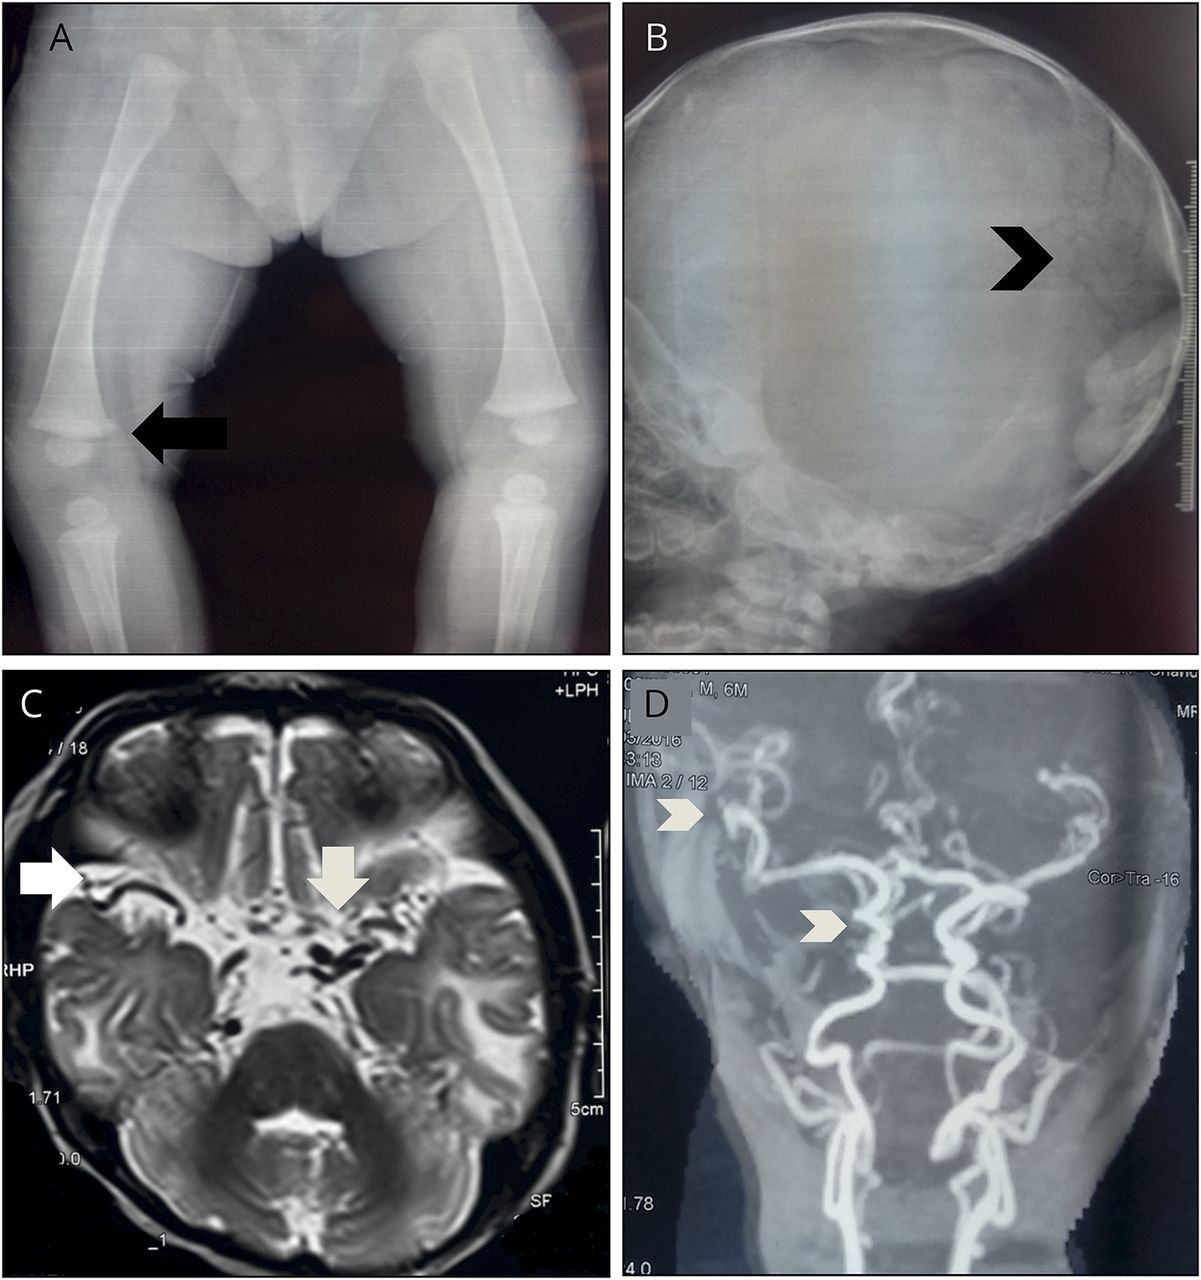

骨骼x射线:(A) metaphyseal热刺和(B) wormian头骨骨(intrasutural骨头)。(C) t2加权MRI轴向截面的基底水池显示多个曲张血管。(D)飞行时间磁共振血管造影显示曲折的颅外和颅内动脉。

第二,受访者表明孩子的骨骼x射线和MRI /大脑磁共振血管造影术(图2中,模拟),要求识别结果的关键。曲折的颅内动脉被55%的受访者正确识别,而曲折的颅外动脉28%。metaphyseal马刺的更微妙的发现是正确确定21%,和wormian骨(额外的骨头在颅缝合线)17%。共有22%的错误识别病人的骨骼异常纤维发育不良;这涉及到替代正常的骨骼有大量纤维基质和不成熟的编织骨和McCune-Albright综合征中可以看到障碍(与性早熟和牛奶咖啡斑)。2